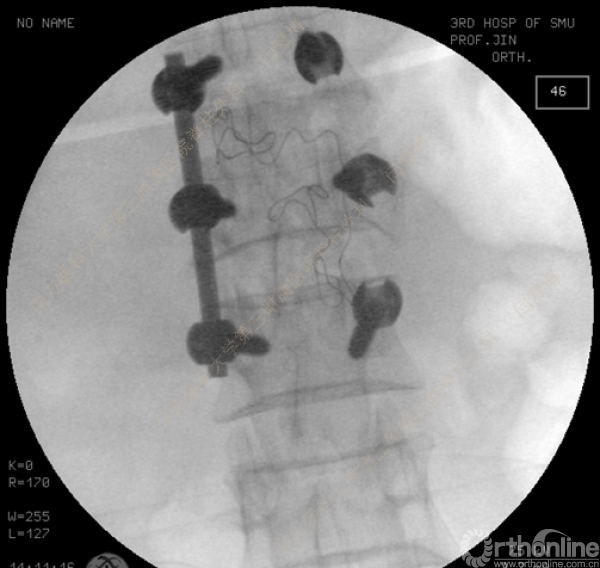

胸腰椎骨折是指由于外力造成胸腰椎骨质连续性的破坏,在如车祸、高处坠落等意外事故中,是最常见的脊柱损伤。老年患者由于本身存在骨质疏松,甚至有可能因为一些如滑倒、跌倒等低暴力因素导致胸腰椎骨折。胸腰椎骨折患者常合并神经功能损伤,且由于致伤因素基本为高能损伤,常合并其他脏器损伤,这为治疗带来了极大的困难和挑战。针对胸腰椎骨折,南方医科大学第三附属医院闫慧博教授介绍了他们运用微创方法治疗的经验。